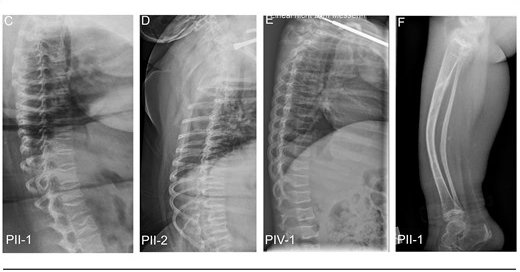

Excited to share our latest work on a novel mutation in a gene that causes non-classical OI👇 TENT5A-Associated Osteogenesis Imperfecta: Long-Term Follow-Up and Molecular Insights

Abstract. OI is a genetically diverse disorder characterized by bone fragility and deformities, with most cases attributed to dominant mutations in collage

📢 New from Project D2 @DFG_FOR2722 : "TENT5A-associated osteogenesis imperfecta: long-term follow-up and molecular insights" Congratulations to Oliver Semler, Frank Zaucke & all co-authors on this important publication! @UKKoeln @BCCologne @UniCologne